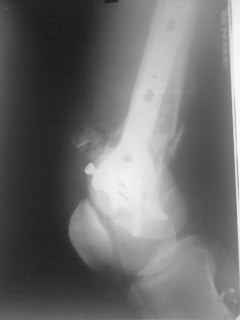

01.12.09г. оперировал больного с подобной травмой в ЦРБ на 4-е сутки после ДТП. Перелом открытый - рана находилась медиально чуть выше надколенника длиной примерно 3-4 см. До этого при поступлении было выполнено ПХО раны и скелетное вытяжение. На момент операции рана без признаков воспаления, состояние больного удовлетворительное.На первичных снимках перелом А3. На операции оказалось С3. Перелом фиксирован мыщелковой пластиной. Для репозиции понадобился медиальный доступ. Медиальный блок дополнен костно-губчатым аутотрансплантатом. На сегодняшний день раны заживают первично, швы еще не сняты, температура тела нормальная, отек бедра значительно уменьшился, имеется анемия средней степени, проводится ЛФК. Фото досылаю